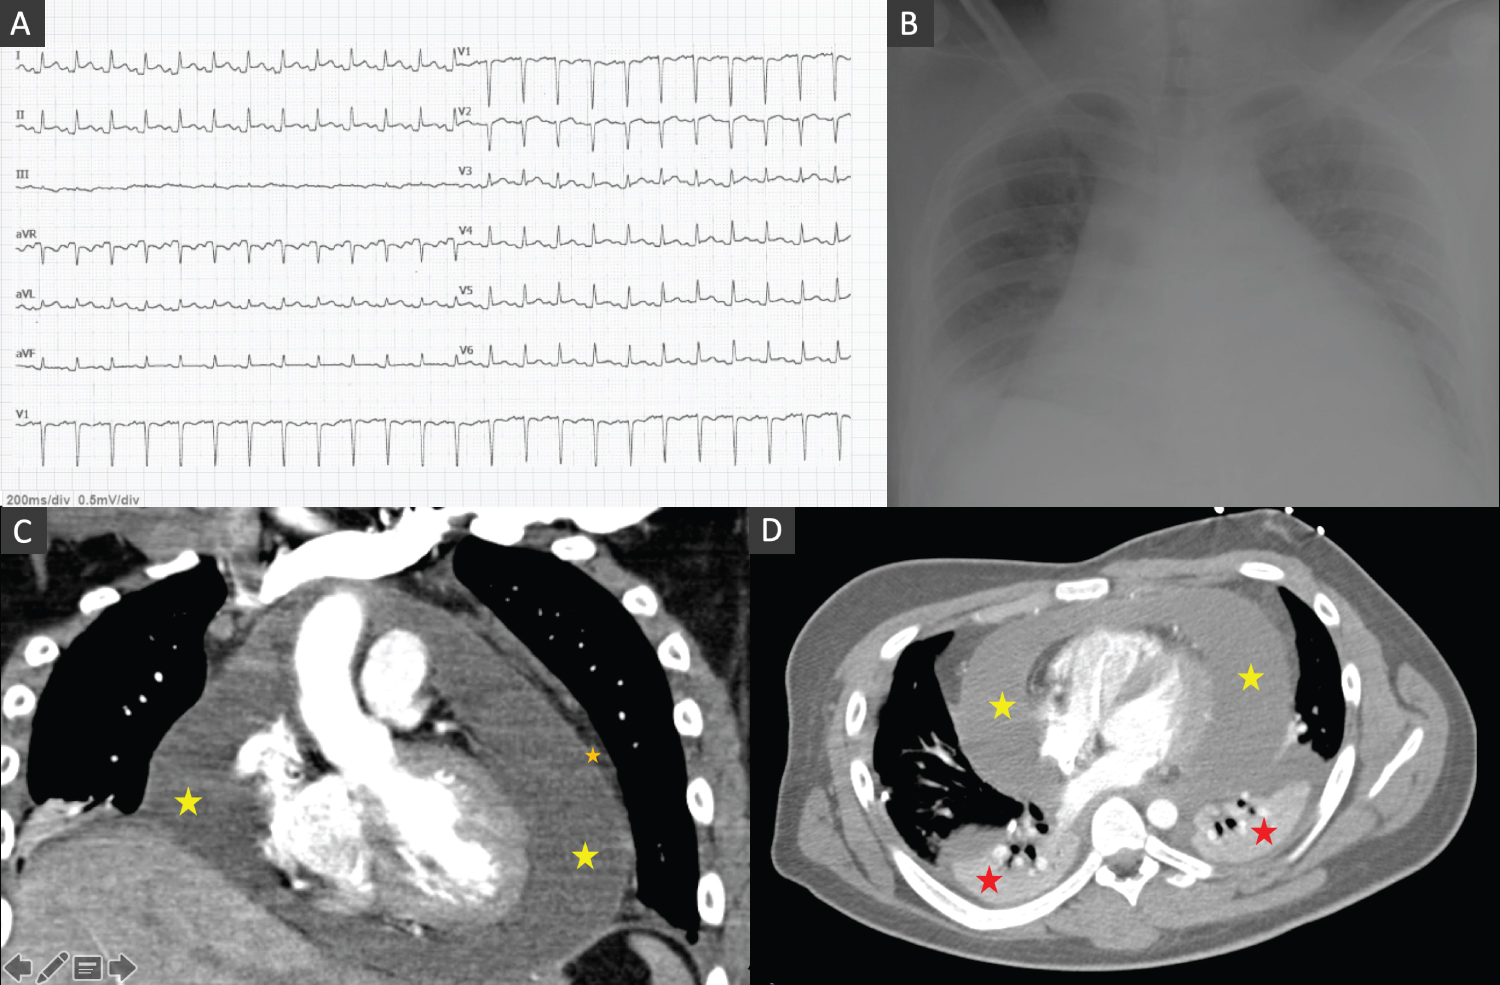

A 19-years-old male patient presented to the emergency department with acute anterior chest pain and fatigue and dyspnoea for two days. The patient had no other complaints including syncope, cough, gastrointestinal or urinary complaints and he had no relevant family or past medical history. On examination his blood pressure was 123/67 mmHg, heart rate 154 bpm, respiratory rate 22 breaths per minute, oxygen saturation 93% in room air and temperature 38.5 °C. Head, eyes, nose, throat and neck examinations were unremarkable. Breath sounds were decreased in the bases with fine crackles. Auscultation of the heart revealed muffled heart sounds. The abdomen was soft and non-tender. The extremities were well perfused with strong and symmetric pulses. No oedema or jugular venous distention was appreciated. Electrocardiogram (ECG) showed sinus rhythm, normal PQ interval, QRS with normal duration and elevation of the ST segment in leads V3-V6, aVL, LI and LII and ST segment depression in aVR (Figure 1A). Arterial blood gas showed mild hypoxemia pO 2 63.8 mmHg and hyperlactacidemia 2.9 mmol/L. Laboratory tests revealed normal haemoglobin Hb 13.6 g/dL, leukocytosis 11.949/uL and neutrophilia 10.500/uL, lymphocytopenia 890/uL and normal platelet count 135.000/uL, elevated C-reactive protein (CRP) 30 mg/dL, elevated procalcitonin 0.48 ng/mL and N-terminal-pro hormone BNP of 632 pg/mL and undetected troponin I. Renal function was normal. Chest radiography showed severe cardiomegaly, bilateral pleural effusion with large right sided pleural effusion and parabronchial cuffing and perihilar haze suggestive of congestion (Figure 1B). Echocardiogram showed normal size ventricles with preserved systolic function, valves with normal morphology and function and a large circumferential pericardial effusion (22-25 mm) without collapse of the cardiac chambers or hemodynamical instability.

Figure 1: (A) ECG showing sinus rhythm, normal PQ interval, QRS with normal duration and elevation of the ST segment in leads V3-V6, aVL, LI and LII and ST segment depression in aVR; (B) Chest radiography showing severe cardiomegaly, bilateral pleural effusion with large right sided pleural effusion and parabronchial cuffing and perihilar haze; (C and D) Thorax-computed tomography confirmed a circumferential pericardial effusion (yellow star) with maximum dimension of 40 mm with a thick pericardium (orange star) and bilateral pleural effusion (red star) (with chest tube inserted in the right fifth intercostal space) in coronal (C) and axial (soft-tissue) view (D). View Figure 1

The patient was admitted to the Intensive Care Unit (ICU) and a right thoracentesis was performed with insertion of a chest drain in the right fifth intercostal space and a total of 600 cc of fluid were drained. Pleural fluid culture was negative and immunohistochemical analysis was compatible with exudate. A thorax-computed tomography confirmed a circumferential pericardial effusion with maximum dimension of 40 mm with a thick pericardium and bilateral pleural effusion (with chest tube inserted in the right fifth intercostal space) (Figure 1B, Figure 1C and Figure 1D). Despite the absence of hemodynamically instability considering the size of the pericardial effusion of unknown etiology a diagnostic and therapeutic pericardiocentesis was executed with draining of a total of 700 cc of sero-hematic fluid. Immunohistochemical analysis was compatible with exudates with inflammatory cells. Autoimmunity laboratory tests were requested. The patient received treatment with empirical antibiotic with amoxicillin, nonsteroidal anti-inflammatory drugs (NSAIDs) and colchicine and remained hemodynamically stable with normalization of the heart rate and resolution of the fever. Lung congestion improved and the chest tube was removed after three days. Two weeks after he was admitted, he was discharged with resolution of the pericardial and pleural effusion and resolution of the inflammatory parameters.